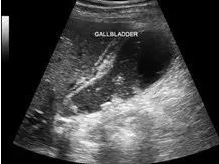

《胆囊疾病,百问百答》是目前专注胆囊方面研究电子书,除了胆囊方面的基础知识,还包括胆囊病例恢复经验,医学影像收集等等都是第一手资料。本电子书作者也是一位胆囊病友,在胆囊疾病治疗过程的日记形式记录胆囊方面的研究,希望帮助广大胆囊病友同时也是帮助自己恢复,也在努力尝试胆囊康复中,期间...